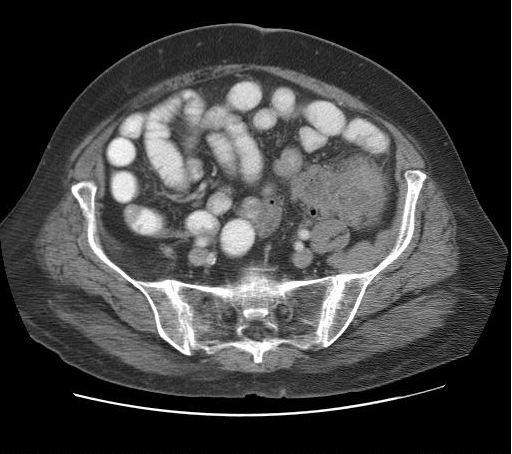

Refer to caption

Question: Identify the specific skeletal joint visible in this image.

Thought Process: The image provided is an axial CT scan of the pelvic region. In such scans, the sacroiliac joint can be identified by its location at the lower end of the spine where the vertebrae meet the ilium bones of the pelvis. This joint appears as a rounded structure on either side of the vertebral column. Given that the scan shows a cross-sectional view through the pelvis, we can confidently identify the sacroiliac joint.

Answer: Sacroiliac.

Figure 9: Qualitative Result Example 2